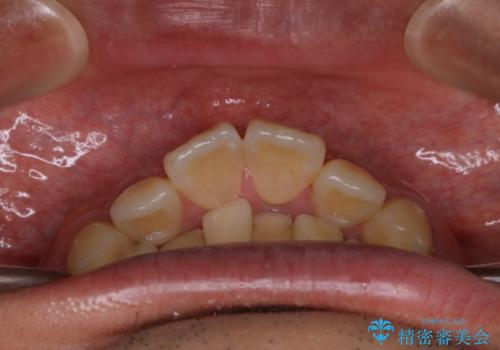

- 上顎前歯の突出感と下顎前歯のガタつきが主訴で来院されました。

出っ歯とガタつきの改善を行うには抜歯が必要と診断し、上下左右第一小臼歯を抜歯する計画を立てました。

抜歯する事で歯の移動量が大きいことからワイヤー表側矯正装置で治療を行うことになりました。

今回のような歯の移動量が大きい場合、インビザライン治療では歯が傾いてしまう場合があります。

また、かみ合わせが深い方の場合、インビザライン治療によってさらにかみ合わせが深くばってしまう場合があります。

ワイヤー治療では歯の傾きを抑えながら大きい距離の移動が可能で、かみ合わせが深くなるリスクも少ないです。